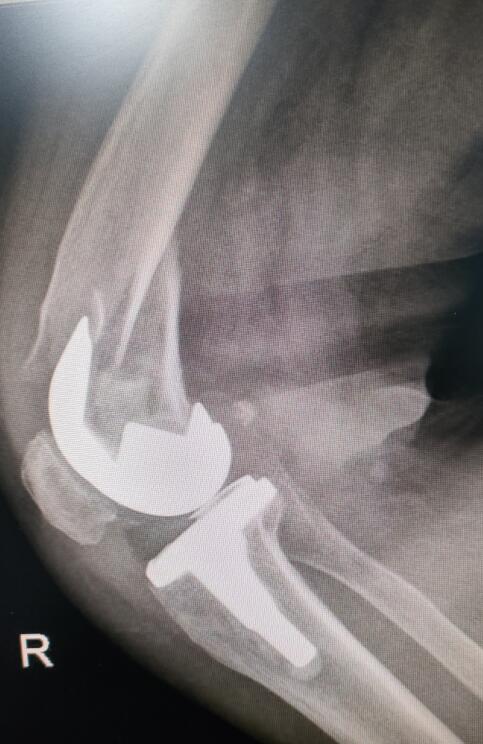

手術(shù)后照片

“關(guān)節(jié)假體需要進行‘翻修’固定,要保證骨折部位修復后假體的穩(wěn)定性,還要考慮患者年齡大,曾接受過多次手術(shù),患有多種基礎(chǔ)疾病,手術(shù)技術(shù)難度高,對醫(yī)生和患者都是一次挑戰(zhàn)?!弊鳛槭中g(shù)團隊成員和吳阿姨主管醫(yī)生的王旌晶覺得一定要對得起患者及家屬這份沉甸甸的信任。

12月7日,在醫(yī)護團隊的默契合作下,歷時1個多小時,吳阿姨的手術(shù)順利完成。經(jīng)過兩周的后續(xù)治療,吳阿姨已經(jīng)可以站起來,借助拐杖行走?!搬t(yī)生們這次又讓我站起來了?!眳前⒁涕_心地說。